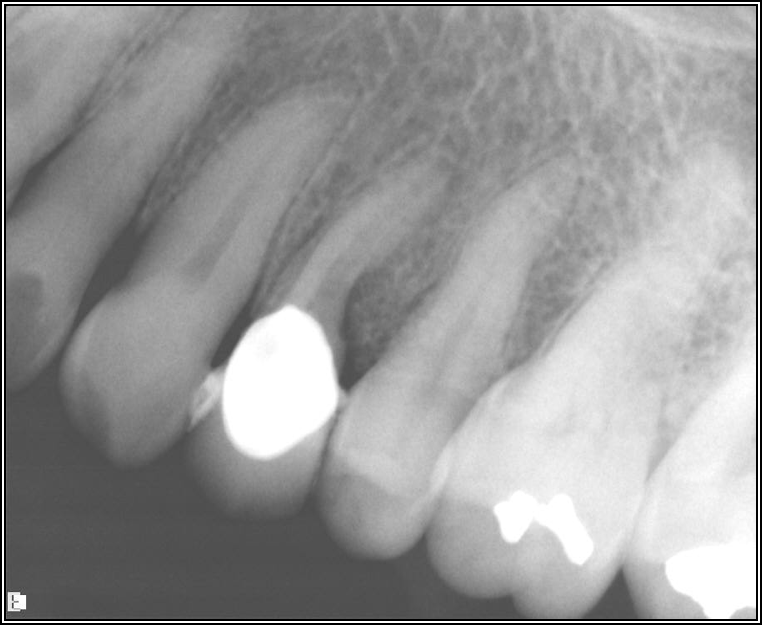

Adjacent Structures

If a tooth stands alone, greater forces will be placed on it because it has no adjacent teeth to provide support. This situation will affect the decision-making process for placing a post. Figure 3 shows a tooth that was on an island and would be having three implants placed in front of it. The tooth would take a much greater beating than another tooth that had support proximally. Even though it had a good root canal, the clinician would need to account for whether the tooth would last until the implants integrated. Figure 4 shows a case that would quickly proceed to implants. The patient had a less-than-ideal bridge for over a decade, with decent endodontics and functionality. There was also an overhang on the premolar. The post was not ideal in this case because there was one distal canal and not all the gutta-percha was removed from it. An intimate fit should be the goal with the post and the walls. Whether using a threaded or non-threaded post, there should not be excess gutta-percha because it is not as solid as the tooth and will lead to greater movement. That movement on the tooth and bridge will create too much force and result in demise.

Fig 4. Case that quickly would proceed to implants.

Figure 4